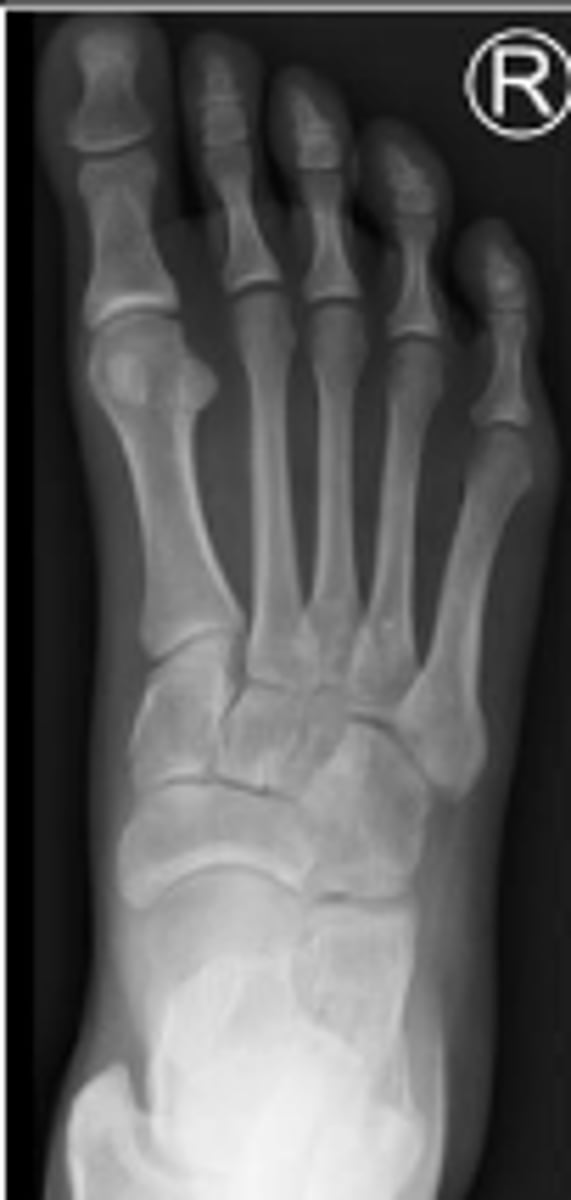

AP right foot

What is the name of the radiographic view?

Cuboid of the right foot

What are the arrows pointing to?

2nd metatarsal of the right foot

What is outlined?

Sesamoid bones of the right foot within the tendon of the flexor hallicus brevis

Medial sesamoid of the right foot within the tendon of the flexor hallicus brevis

Head of the talus of the right foot

Calcaneus of the right foot

Navicular of the right foo

Medial malleolus of the right foot

What is the arrow pointing to?